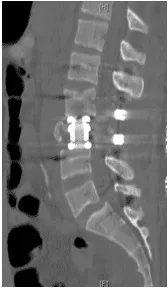

Patient was operated and the spinal canal cleaned up of all bony fragments. The spine was fixed from the side and the back to take care of instability.

Patient was sent to a rehab facility after the surgery and she made a quick and complete recovery in 5-6 months.